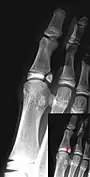

Salter–Harris fracture types

There are nine types of Salter–Harris fractures; types I to V were originally described,[3] and types VI to IX were added subsequently:[5]

• Type I – transverse fracture through the growth plate (also referred to as the "physis"):[6] 6% incidence

• Type II – A fracture through the growth plate and the metaphysis, sparing the epiphysis:[7] 75% incidence, takes approximately 12-90 weeks or more in the spine to heal.[8]

• Type III – A fracture through growth plate and epiphysis, sparing the metaphysis:[9] 8% incidence

• Type IV – A fracture through all three elements of the bone, the growth plate, metaphysis, and epiphysis:[10] 10% incidence

• Type V – A compression fracture of the growth plate (resulting in a decrease in the perceived space between the epiphysis and metaphysis on x-ray):[11] 1% incidence